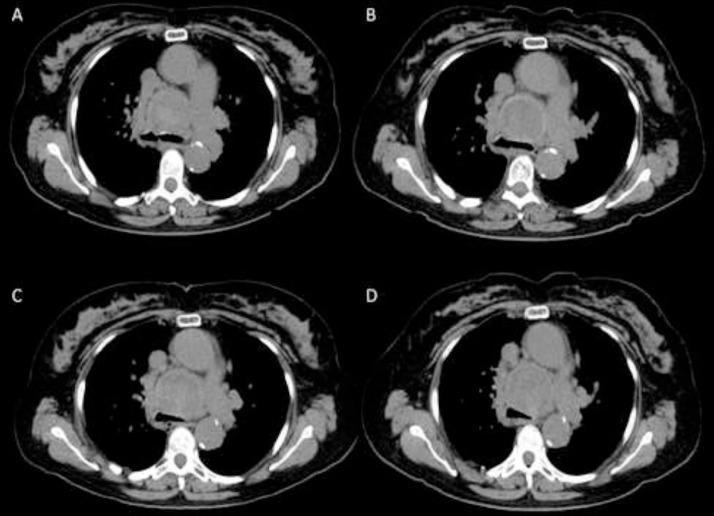

Bronchial artery aneurysm and pseudoaneurysm is a rare but life-threatening diagnosis due to catastrophic complications from rupture. Prompt detection and management is key to prevent complications. CT angiogram and digital subtraction angiography are preferred diagnostic imaging modalities. Being very uncommon, these entities can be misdiagnosed as a nonspecific mediastinal soft tissue mass, which can lead to delay in diagnosis and inappropriate or delayed management. We present a case of 72-year-old woman with incidentally detected large bronchial artery pseudoaneurysm, incorrectly classified as mediastinal malignancy at outside facility, receiving follow-up exams for 2 years, before correct diagnosis and management.

支气管动脉动脉瘤和假性动脉瘤是一种罕见但危及生命的诊断,因为破裂会引发灾难性并发症。及时检测和处理是预防并发症的关键。CT血管造影和数字减影血管造影是首选的诊断成像方式。由于非常罕见,这些病变可能被误诊为非特异性纵隔软组织肿块,从而导致诊断延迟以及治疗不当或延误。我们报告一例72岁女性病例,其偶然发现巨大支气管动脉假性动脉瘤,在外院被错误分类为纵隔恶性肿瘤,接受了2年的随访检查,最终才得以正确诊断和处理。